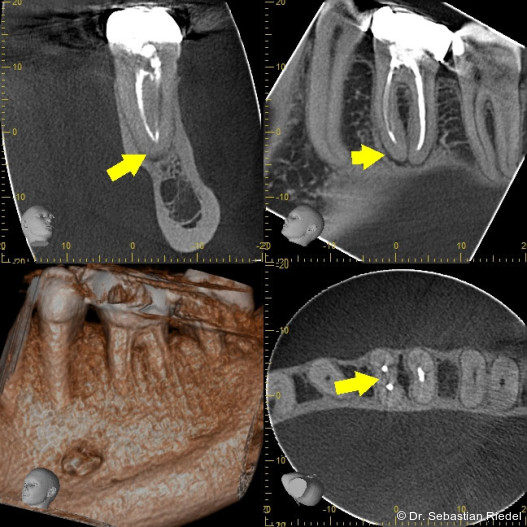

Die Präparation des Zahnes erfolgt entsprechend der anatomischen Lage der Wurzelkanaleingänge – bewährte Schemata dafür liegen vor. Die Möglichkeit der dreidimensionalen Dia­gnostik mittels DVT bietet einen zusätzlichen Schutz, um wertvolle Zahnhartsubstanz zu erhalten und trotzdem einen geradlinigen Zugang zu den Kanalorifizien zu ermöglichen.

Auch bei den Revisionen kommt meiner Meinung nach der geradlinigen Zugangspräparation zu den Wurzel­kanal­ein­gängen eine immens wichtige Aufgabe zu: Die auf die Präparationsinstrumente wirkenden Kräfte können so signifikant besser kon­trolliert werden. Aber auch die modernsten Legierungen können trotz aufwendiger Herstellungsverfahren bei unangemessener Krafteinwirkung frakturieren. Wir können die Wahrscheinlichkeit für Frakturen aber durch sachgemäße Benutzung fast auf Null reduzieren.

Bei Revisionen strebe ich ebenfalls an, in mindestens zwei Arbeitsschritten bis nach apikal zu kommen: Im ersten „Durchgang“ wird das koronale und eventuell das mittlere Kanaldrittel von Fremdmaterial und kontaminiertem Gewebe befreit. Je nach Komplexität der Anatomie kann schon im zweiten „Durchgang“ mit den Instrumenten bis nach apikal präpariert werden. Wenn die dafür aufzuwendende Kraft aber zu groß ist, sollte die Kanal­präparation in weitere Teilschritte untergliedert werden.